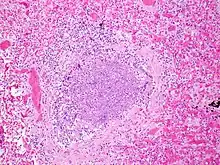

.jpg)

The term usually refers to acute viral bronchiolitis, a common disease in infancy. This is most commonly caused by respiratory syncytial virus[12] (RSV, also known as human pneumovirus). Other agents that cause this illness include human metapneumovirus, influenza, parainfluenza, coronavirus, adenovirus, rhinovirus and mycoplasma.[13][14]